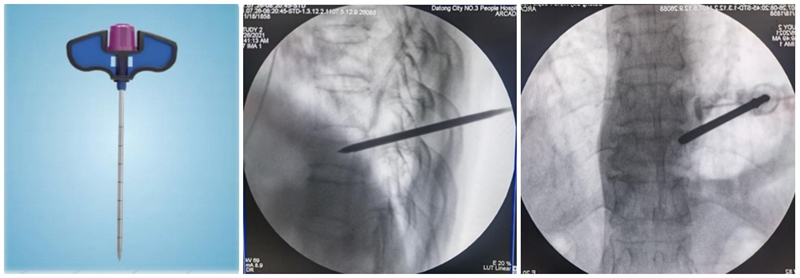

(6)注入骨水泥:应用骨水泥灌注管灌注骨水泥时,由聚醚醚酮树脂制成的灌注管在骨水泥灌注完成后要及时拔除,避免椎体内骨水泥硬化后无法拔出;椎体穿刺侧骨水泥灌注不满意,可拔除输送套管,直接连接穿刺套管,进行二次灌注。

术后行影像学检查,显示骨水泥弥散满意,达到了单侧穿刺,双侧弥散的效果,无渗漏